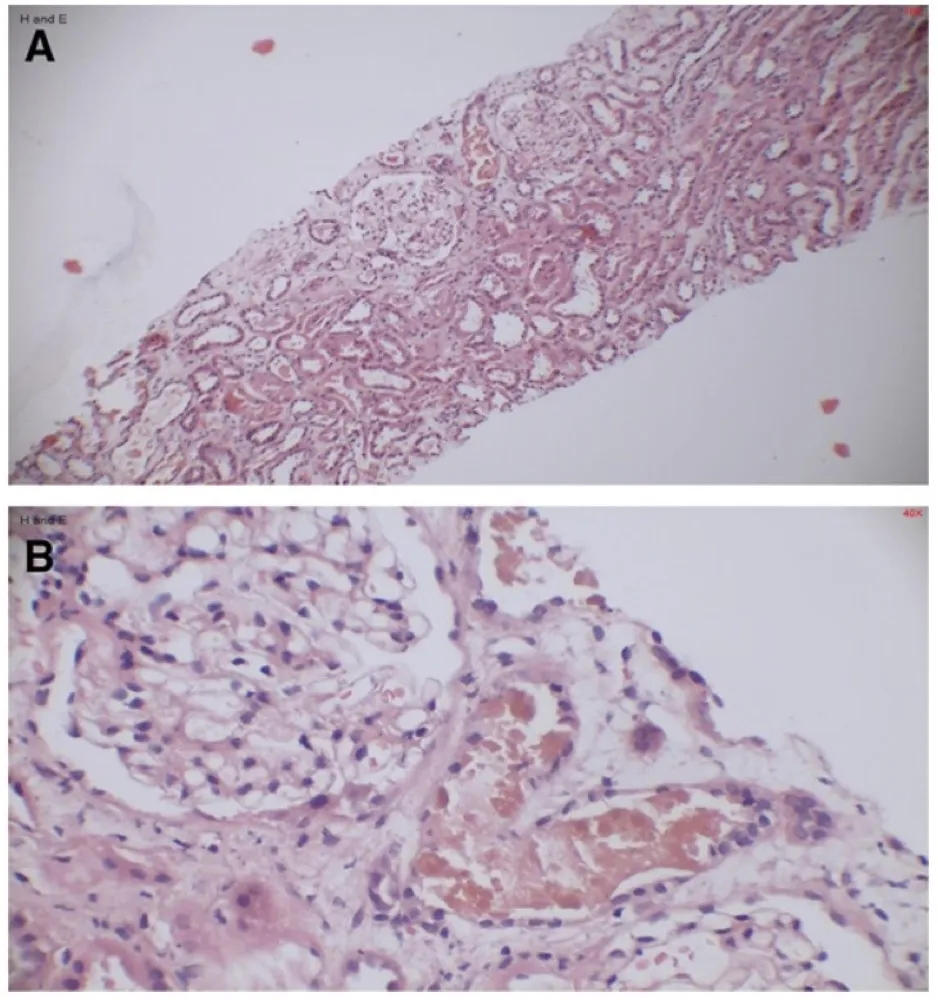

IRA + Icterícia: Um Caso que Exige Investigação Detalhada

IRA + Icterícia: Um Caso que Exige Investigação Detalhada